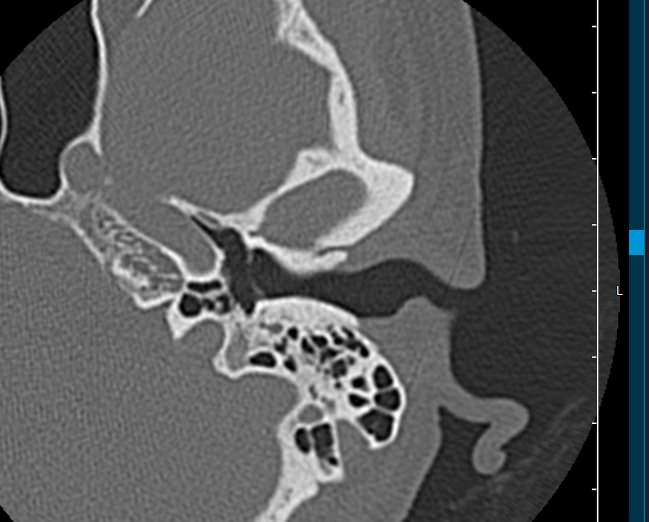

Височные кости имеют сложное строение. Они участвуют в образовании боковых стенок и части основания черепа. Кроме того, в них находятся важные органы слуха и равновесия: в среднем ухе расположен слуховой орган, во внутреннем ухе – вестибулярный аппарат. В костных каналах височных костей проходят нервные волокна лицевого, преддверно-улиткового и тройничного нервов.

Мультиспиральная КТ позволяет детально визуализировать все вышеперечисленные анатомические структуры височных костей, диагностировать заболевания среднего и внутреннего уха.

КТ наиболее информативна при черепно-мозговых травмах, воспалительных заболеваниях уха, опухолевых процессах этой области. При компьютерной томографии возможно проследить ход барабанной перепонки, оценить структурность и положение слуховых косточек (молоточка, стремечка и наковальни), оценить объем и расположение содержимого в антральной клетке или ячейках сосцевидного отростка височной кости.

На основании полученных данных цифровые приложения томографов создают трехмерные реконструкции анатомической зоны исследования. Это дает возможность наглядно увидеть пространственное расположение органов, что бывает особенно важно при планировании операций.